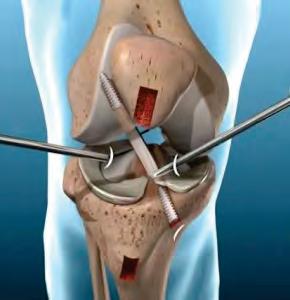

Alta especialidad en Cirugía de rodilla y cadera

• Artroscopía

• Prótesis de rodilla y cadera

• Lesiones ligamentarias y tendinosas